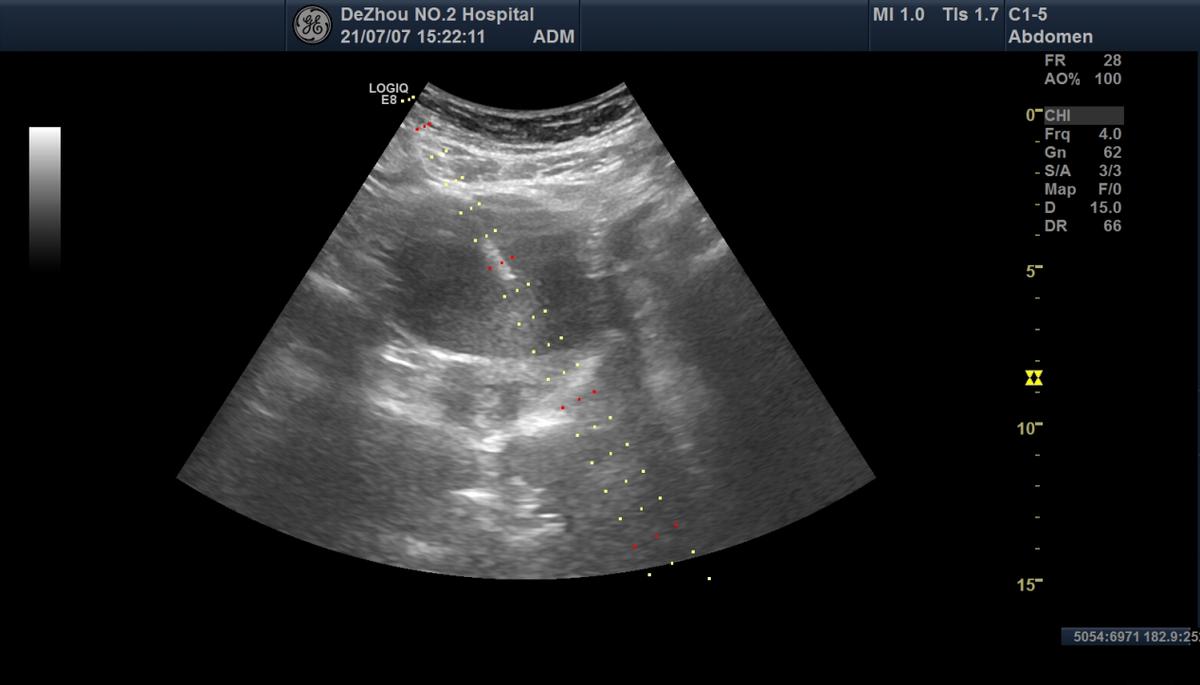

准备超声引导下穿刺

穿刺针进入巧克力囊肿内